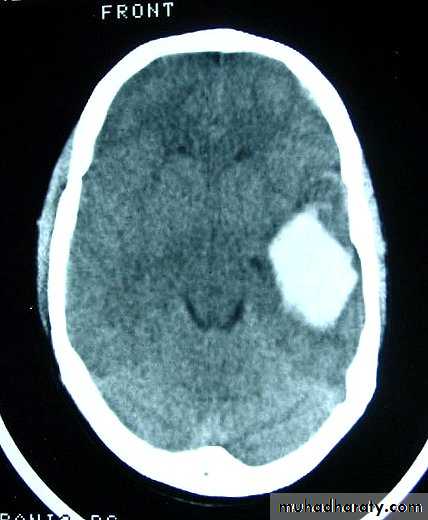

b. Subdural Haematoma

They are the most common intracranial mass lesions resulting from head trauma.They are classified depending on how long they take to present clinically following the injury into:

Chronic Subdural Haematoma

Most common in infants and in adults over 60 years of age secondary to SLIGHT blow to the head which may pass unnoticed.Source of bleeding (haematoma): usually from bridging veins as they pass to the venous sinuses.

The patients present with progressive neurological deficits more than 3 weeks after the trauma.

The initial head injury is often completely forgotten.

CT scan: the acute clotted blood is initially appears white (hyperdence), but as it liquefies, it slowly becomes black (hypodense).

They should be drained if they continue to enlarge.

They are evacuated by drilling burrholes over the collection and washing it out with warmed saline.